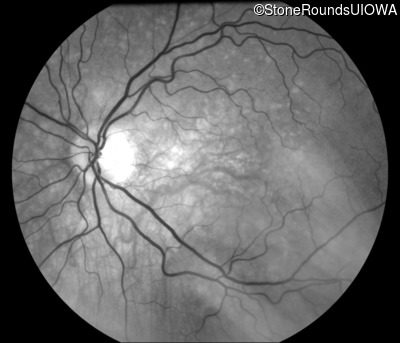

Fundus Photography - Left - 20/15 -1 sc

Exemplar